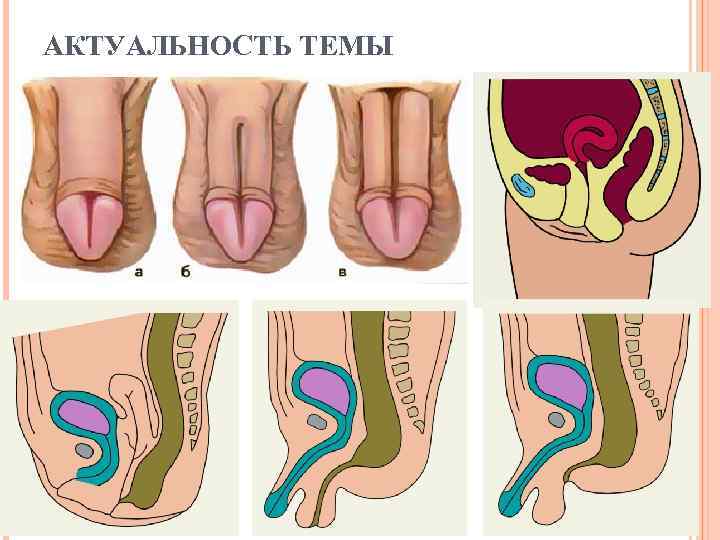

АКТУАЛЬНОСТЬ ТЕМЫ

АКТУАЛЬНОСТЬ ТЕМЫ